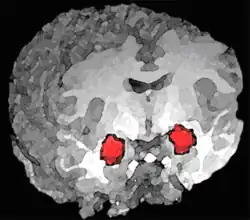

- Amígdala cerebral. Algunos estudios basados en diversas técnicas de exploración por imágenes muestran que los mecanismos cerebrales subyacentes a la impulsividad, inestabilidad emocional, agresividad, ira y emociones negativas podrían estar en una desregulación de los circuitos neuronales que modulan las emociones. En especial, se han observado pequeñas diferencias individuales en como se regula la amígdala, un núcleo cerebral que desencadena el pánico o la ira en respuesta a estímulos de peligro procedentes de otras áreas cerebrales. Algunos individuos tienen dificultades para inhibir esta respuesta desde el área prefrontal. Se sabe que el abuso de substancias o el estrés empeoran esta capacidad de inhibición.[25][26] En 2003 se realizó un estudio sobre afectados de TLP, viendo que mostraban una actividad significativamente superior en la amígdala izquierda, en comparación con sujetos normales. Algunos pacientes con este trastorno incluso tenían dificultades para clasificar caras neutras, que veían como amenazantes.[27]

Otros estudios han encontrado una disminución de tamaño significativa en el volumen del hipocampo y de la amígdala en síndromes con síntomas disociativos.[29] La diferencia de tamaño del hipocampo, una estructura cerebral relacionada con la memoria, se ha establecido en un promedio de un 16 % menor (Driesden y otros, 2000) lo cual podría explicar dos rasgos asociados al TLP, la dificultad para aprender de la experiencia y los problemas para generar una identidad. En cuanto a la disminución de volumen en la amígdala, estudios posteriores llevados a cabo por Tebartz (2007) confirmaron las cifras iniciales, encontrando un aumento correspondiente en la amígdala izquierda del 17 % en los contenidos de creatina, posiblemente para compensar un deterioro en las redes neuronales.[30]